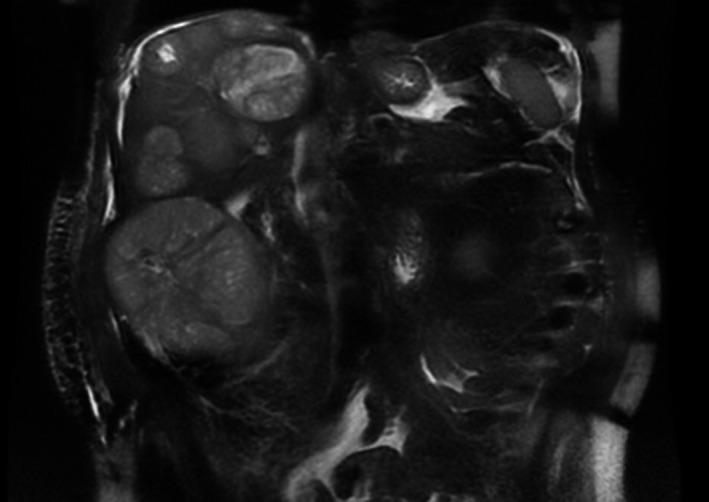

转移性神经内分泌癌表现为多灶性肝病变伴甲胎蛋白升高。

Metastatic neuroendocrine carcinoma presenting as multifocal liver lesions with elevated alpha-fetoprotein.

Significant elevations in alpha-fetoprotein should raise suspicion for hepatocellular carcinoma as malignancies with metastasis to the liver can elevate the alpha-fetoprotein level but typically <300 ng/mL. Diagnosis should be confirmed with typical characteristics of hepatocellular carcinoma on imaging and or liver biopsy to confirm diagnosis.

甲胎蛋白显著升高应引起对肝细胞癌的怀疑,因为转移至肝脏的恶性肿瘤可使甲胎蛋白水平升高,但通常<300 ng/mL。诊断应通过影像学上肝细胞癌的典型特征和/或肝活检来确诊。